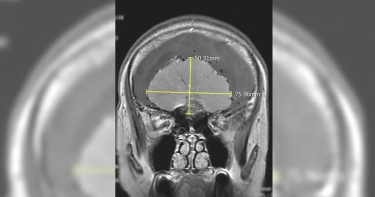

心情低落以為是憂鬱症 一查竟是腦瘤

58歲邱女士日前突然變得疲倦消極,以為自己是身心方面出了狀況,故而至身心醫學科門診,經醫師問診後發現邱女士出現步行不穩、視力模糊、嗅覺喪失等症狀,便安排核磁共振造影,赫然發現她前顱底有一8公分的巨大腦瘤,遂轉診至神經外科進行腦瘤全切手術,成功摘除巨大腦膜瘤,1週後平安出院。腦膜瘤生長緩慢 易頭暈噁心、嗅覺與情緒變化台北慈濟醫院神經外科醫師李定洲指出,腦膜瘤的發生率佔整體腦瘤的三分之一,尤其好發於30歲至50歲成人,其中以女性居多,男女比約1:2。腦膜共有三層,由外到內依序是硬腦膜、蜘蛛網膜及軟腦膜,腦膜瘤的成因主要來自蜘蛛網膜的帽狀細胞增生,常生長於大腦半球的圓凸部、蝶谷脊、矢狀竇旁等部位。大多數腦膜瘤生長速度緩慢,其出現的症狀取決於其生長位置與速度,以邱女士為例,前顱底由額骨的框板、蝶谷體前部、蝶谷小翼和篩骨的篩板構成,容納大腦半球的額葉,額葉掌控人體的自主行為,如負責行走行為、視覺感知、長期記憶與情緒控制,一旦腦膜瘤生長於前顱底,便會造成額葉損傷,因而出現頭暈頭痛、噁心嘔吐、嗅覺喪失、視力減退、情緒變化等臨床表徵。腦瘤全切手術為主 放術治療聚焦病灶腦膜瘤的治療以腦瘤全切手術為準則,透過高速氣鋸打開適當大小的頭骨將腦膜瘤剝離後取出,但開顱手術仍會存在無法完整摘除的可能,因此可採用立體定位放射治療,藉由三度空間立體定位的方法將多個放射線射束集中於顱內病灶,以發揮定點、聚焦的治療效果,亦能避免周邊正常組織受到不必要的照射。劇烈頭痛、神經功能異常 務必就醫診治李定洲提醒,若是出現劇烈頭痛及神經功能異常時,務必及時就醫;同時也建議具有家族史或神經學症狀異常的40歲以上成人定期接受核磁共振造影或電腦斷層檢查,從而早期發現、早期治療。

神采奕奕變疲倦消極…58歲婦「嗅覺喪失」就醫 前顱驚見8巨瘤

本來整日都神采奕奕的58歲邱女士日前突然變得疲倦消極,以為自己是身心方面出了狀況,故而至台北慈濟醫院身心醫學科門診。醫師問診後發現,邱女出現步行不穩、視力模糊、嗅覺喪失等症狀,便安排核磁共振造影,結果顯示患者前顱底有一顆8公分的巨大腦瘤,遂轉診至神經外科門診。李定洲醫師予以腦瘤全切手術,成功摘除巨大腦膜瘤,1週後平安出院。李定洲醫師指出,腦膜瘤的發生率佔整體腦瘤的三分之一,尤其好發於30歲至50歲成人,其中以女性居多,男女比約1:2。腦膜共有三層,由外到內依序是硬腦膜、蜘蛛網膜及軟腦膜,腦膜瘤的成因主要來自蜘蛛網膜的帽狀細胞增生,常生長於大腦半球的圓凸部、蝶谷脊、矢狀竇旁等部位。醫師說明,大多數腦膜瘤生長速度緩慢,出現的症狀取決於其生長位置與速度,以邱女士為例,前顱底由額骨的框板、蝶谷體前部、蝶谷小翼和篩骨的篩板構成,容納大腦半球的額葉,額葉掌控人體的自主行為,如負責行走行為、視覺感知、長期記憶與情緒控制,一旦腦膜瘤生長於前顱底,便會造成額葉損傷,因而出現頭暈頭痛、噁心嘔吐、嗅覺喪失、視力減退、情緒變化等臨床表徵。李定洲醫師提醒,若是出現劇烈頭痛及神經功能異常時,務必及時就醫。(圖/台北慈濟醫院提供)李定洲表示,腦膜瘤的治療以腦瘤全切手術為準則,透過高速氣鋸打開適當大小的頭骨將腦膜瘤剝離後取出,但開顱手術仍會存在無法完整摘除的可能,因此可採用立體定位放射治療,藉由三度空間立體定位的方法將多個放射線射束集中於顱內病灶,以發揮定點、聚焦的治療效果,亦能避免周邊正常組織受到不必要的照射。李定洲醫師提醒,若是出現劇烈頭痛及神經功能異常時,務必及時就醫;同時也建議具有家族史或神經學症狀異常的40歲以上成人定期接受核磁共振造影或電腦斷層檢查,從而早期發現、早期治療。